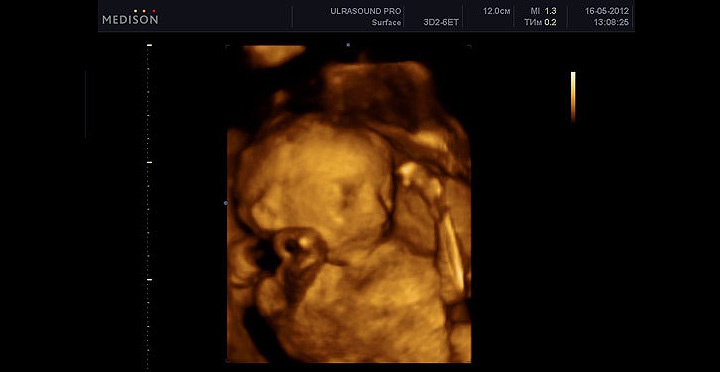

УЗИ

УЗИ на этом сроке не является обязательным, но может быть назначено для уточнения срока родов и оценки развития органов.

Анализируется формирование позвоночника, сердца и замеры параметров плода.

Фетометрия (размеры плода)

- БПР (бипариетальный размер) 58–70 мм.

- ЛЗ (лобно-затылочный размер) 73–89 мм.

- ОГ (окружность головки плода) 214–250 мм.

Нормальные размеры длинных костей

- Бедренная кость 42–50 мм.

- Плечевая кость 39–47 мм.

- Кости предплечья 33–41 мм.

- Кости голени 38–46 мм.

Если высота дна матки отклоняется от нормы, УЗИ поможет определить количество околоплодных вод и размеры малыша. Мало- или многоводие могут указывать на проблемы.

При УЗИ также оценивается состояние матки, особенно если были операции. Истончение рубца на матке до 2 мм может угрожать разрывом, поэтому необходимо внимательно следить за состоянием.